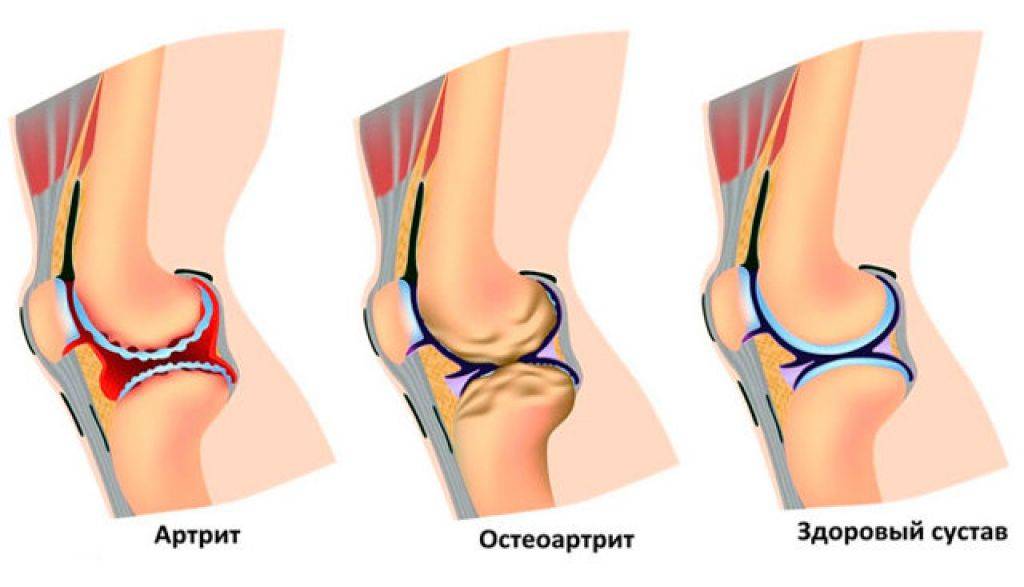

Артрит. Воспалительный процесс в суставе приводит к расслоению, истончению и трещинам хрящевой ткани. Если заболевание не лечить, изменения со временем затрагивают и кость: на ней появляются наросты, уплотнения и шипы. Далее происходит деформация кости, из-за чего возникают отеки и сильные боли даже в состоянии покоя.

- Артрит (воспаление одного или нескольких суставов). Изменения в хрящевой ткани при артритах проявляется трещинами, расслоением, истончением, что приводит к появлению скрипения при движениях в суставе. Кроме того, хруст и треск связаны с изменениями в костной ткани — появлением уплотнений, шипов, наростов.